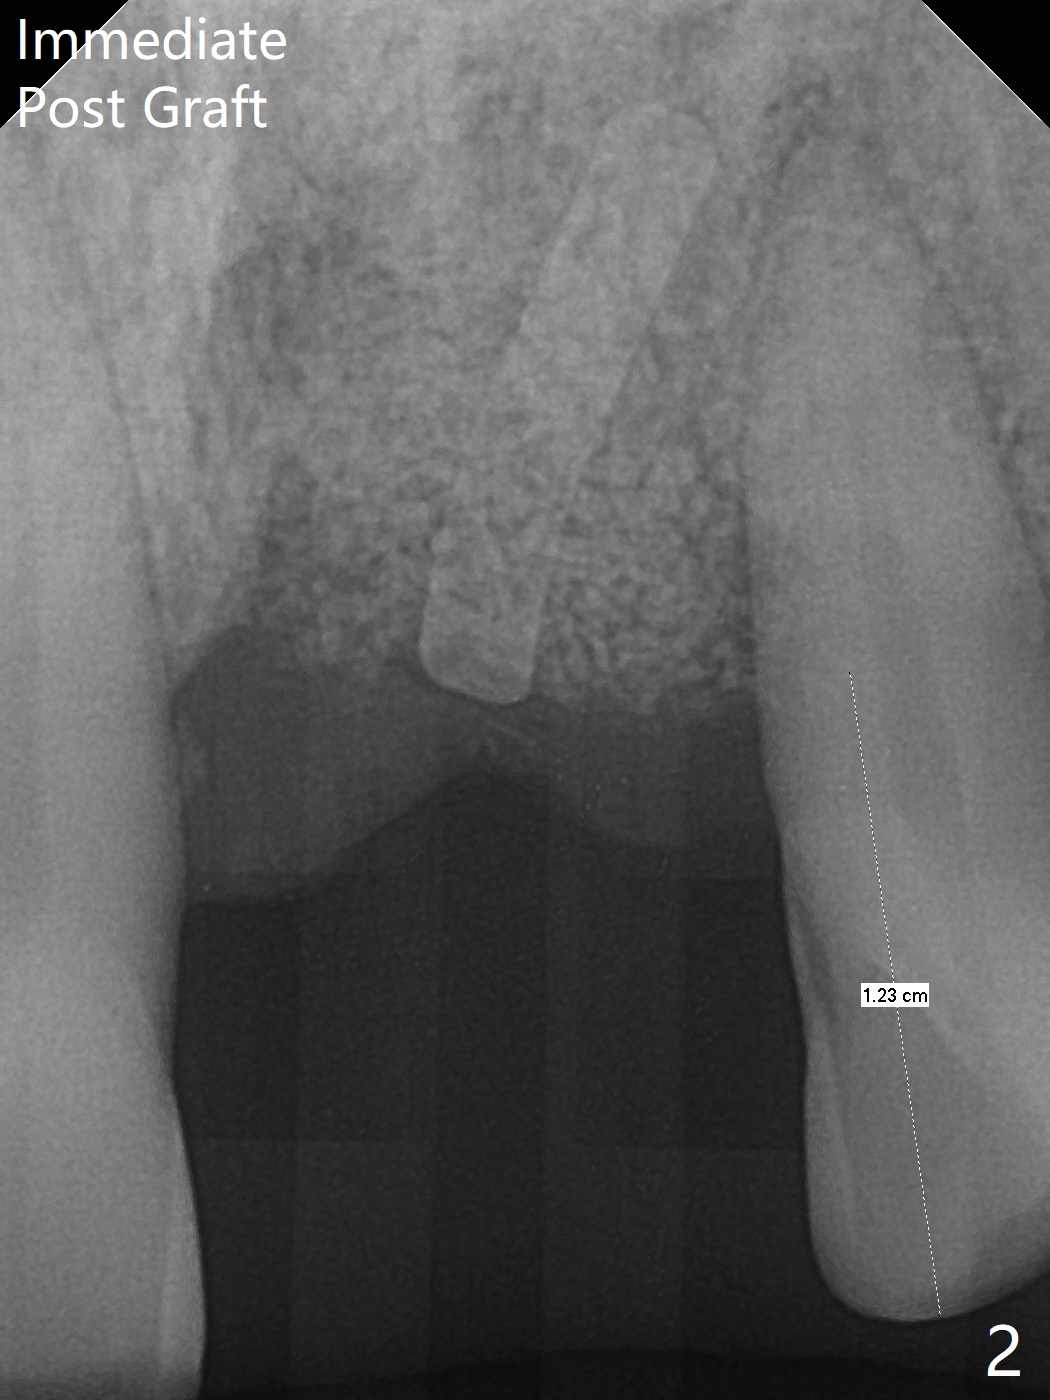

左上1(图一)拔除,植骨,使用带钛架不可吸收膜(图二)后十个月准备植牙(图三),在没有术中根尖片指导下(导板习惯),在牙槽嵴正中开始钻洞,第一个钻头最后一两个毫米觉得有突破感,但是颊侧舌侧没有穿孔,然后植入3.5x11.5毫米植体(图五,扭力>35 Ncm),术后射线表明植体接近切牙管(图四:*)。考虑到病人要离城,颊侧第一螺纹暴露(图六),舌侧骨板薄(图五),植骨,放置愈合基台(图七)。 术后十一天CT显示植体没有侵犯切牙管(图八:I);植体颊侧骨粉(箭头)似乎可以解释颊侧饱满(图九)。第二原因是减张缝合,胶原膜暴露(*),而下面骨粉没有暴露,以后伤口应该是二期愈合。